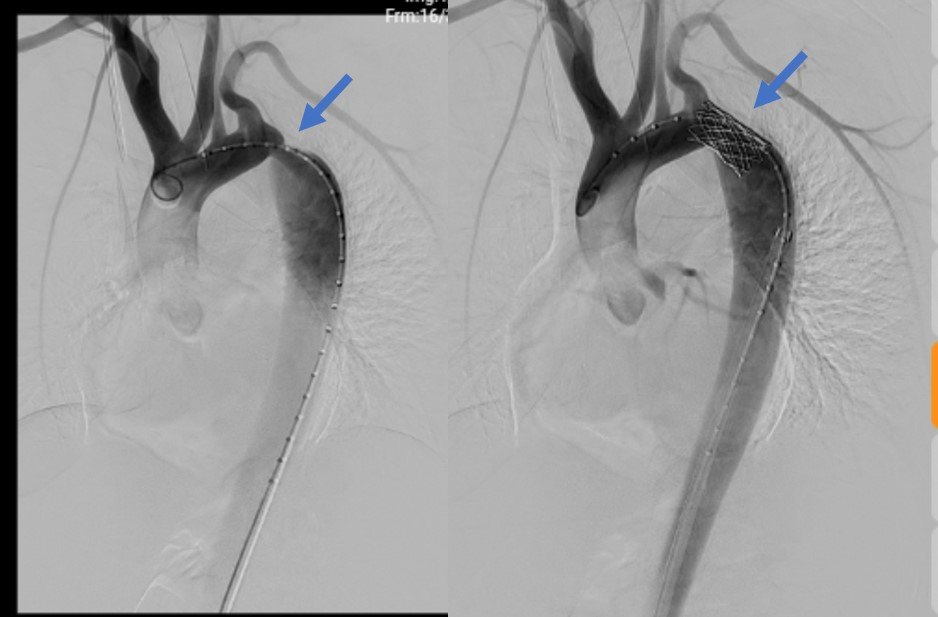

cp支架治疗重度主动脉缩窄一例(唐都医院首例)

图片尺寸714x934